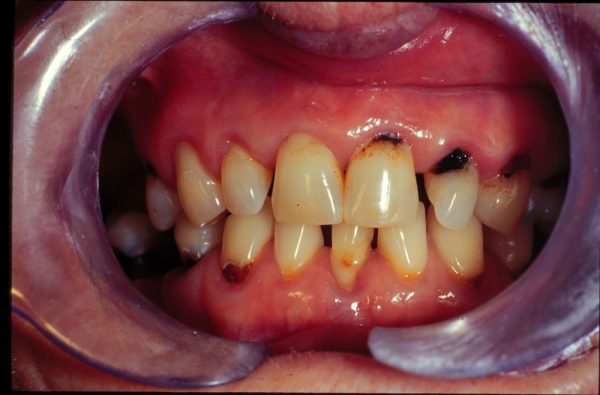

پوسیدگی و حفره دندان

پوسیدگی دندان چگونه به نظر می رسد؟ در مراحل اولیه، پوسیدگی به شکل یک نقطه کوچک سفید یا قهوه ای روی دندان شما ظاهر خواهد شد. ممکن است نتوانید متوجه این موضوع شوید اما دندانپزشک شما می داند دنبال چه چیزی باشد.

آیا نقاط سیاه روی دندان به معنای حفره هستند؟

اگر روی دندان های خود یا بین آنها دارید لکه های سیاه کوچک دارید و در نتیجه خوردن توت سیاه یا مسواک زدن با ذغال فعال ایجاد نشده است، ممکن است کاملاً یک حفره باشد.

لکه های قرمز یا قهوه ای ممکن است به معنای پوسیدگی دندان باشند و لکه های قهوه ای یا سیاه ممکن است حفره باشند.

علاوه بر این، حفره های دندان می توانند به شکل پوسیدگی سیاه دندان نیز ظاهر شوند. دندان پوسیده سیاه چیزی است که نیاز به مراقبت فوری دندانپزشکی دارد، بنابراین بسیار مهم است که در صورت مشاهده هر یک از این علائم، به دندانپزشک مراجعه کنید.